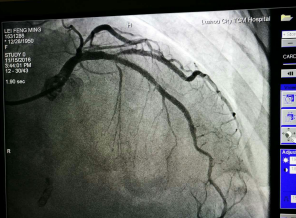

近日,我院成功應(yīng)用切割球囊為一例冠脈內(nèi)支架再狹窄的患者進(jìn)行了冠脈內(nèi)成形術(shù),解除了患者胸悶胸痛癥狀。據(jù)了解,此項(xiàng)技術(shù)的開展在我市市屬醫(yī)院中尚屬首次,該技術(shù)的開展為冠脈支架內(nèi)再發(fā)狹窄的患者帶來福音。??切割球囊???? 老人支架植入后再發(fā)心絞痛 ???冠脈內(nèi)切割球囊成形術(shù)解決難題70多歲的周阿姨兩年前因...